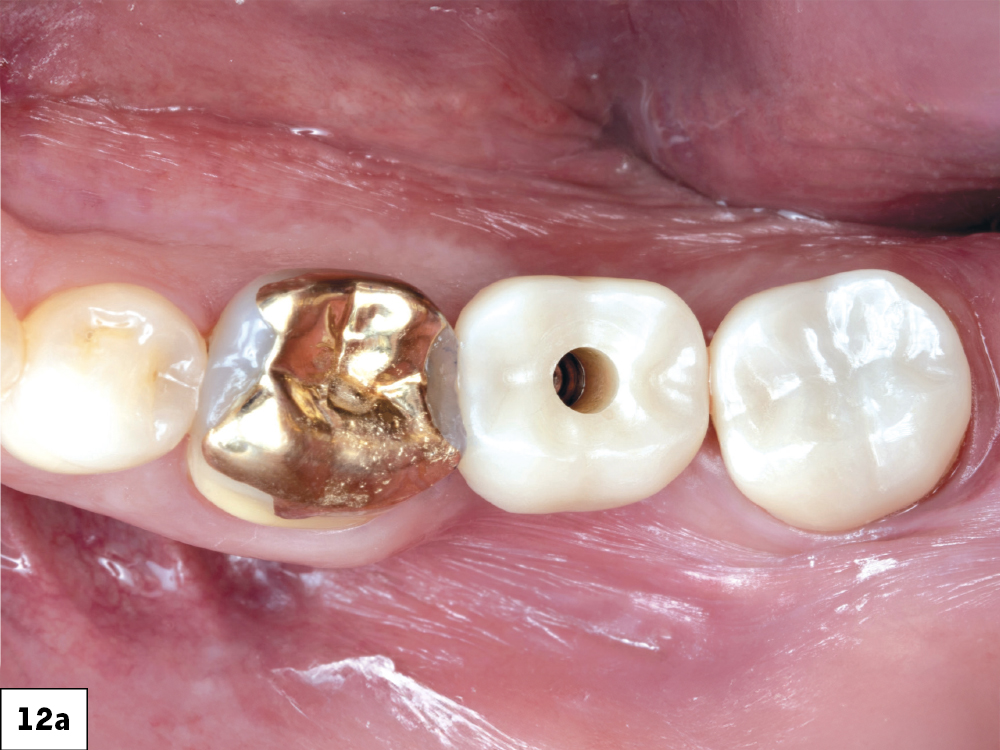

In-office milling is a quickly evolving option for the modern dental practice. With the introduction of a same-day screw-retained option, BruxZir® NOW SRC milling blocks, there’s even more opportunity for optimizing single-unit restoration workflows. In this case study, I’ll demonstrate how this product can be used as part of an efficient workflow for tooth replacement in the posterior. When combined with guided surgery and in-office crown design, this procedure offers reliable results while saving money and significantly cutting down on chair time for dentists.